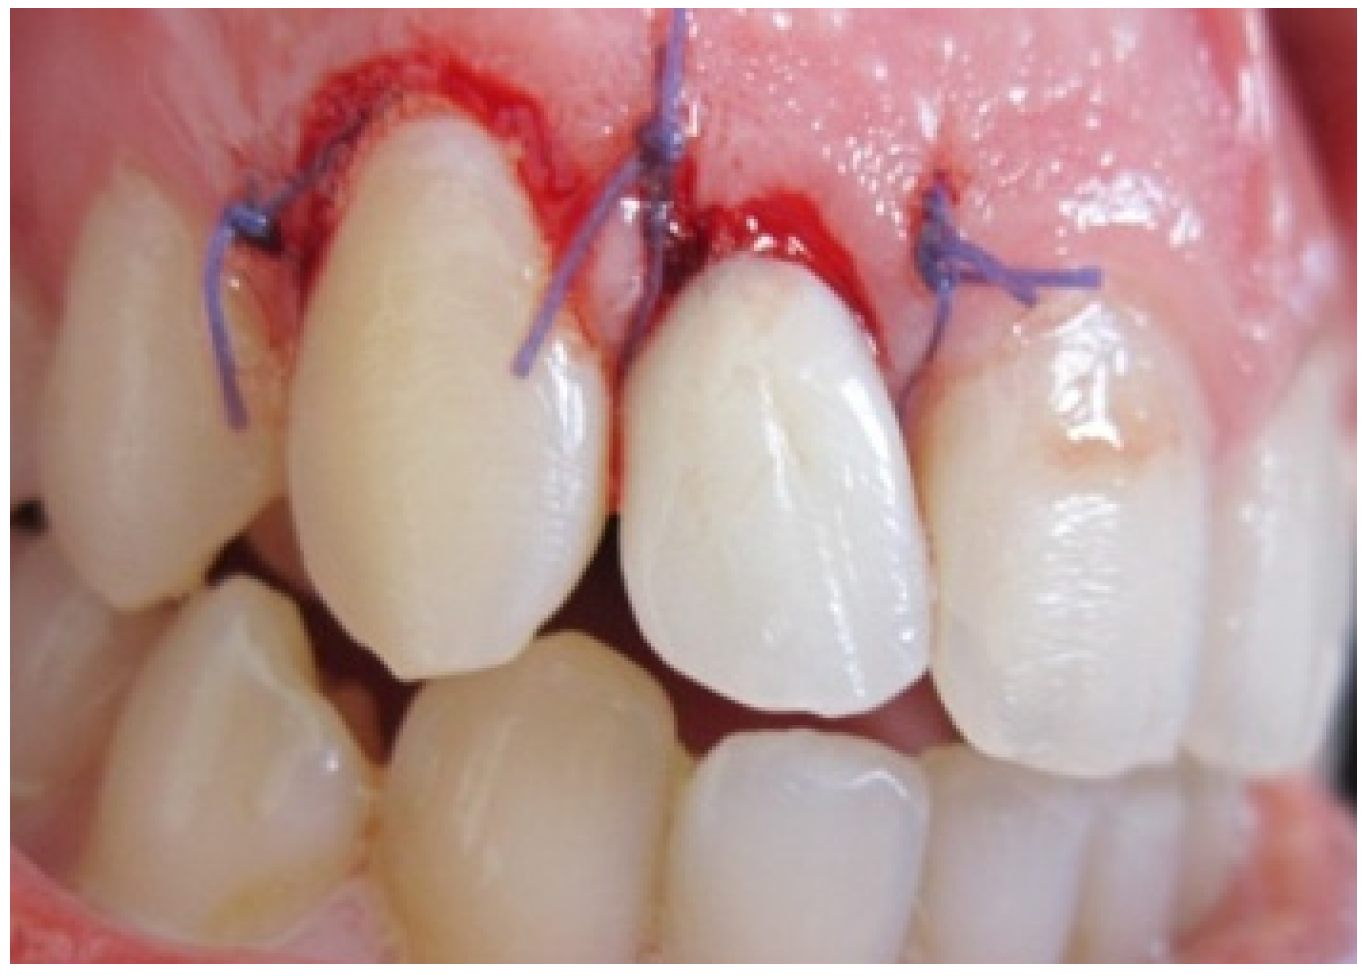

Sutures were finally advocated after reapplication of the gingiva to provide a healing less exposing the operation site to the oral environment (Figure 4) [18].

Figure 4. Crown lengthening.